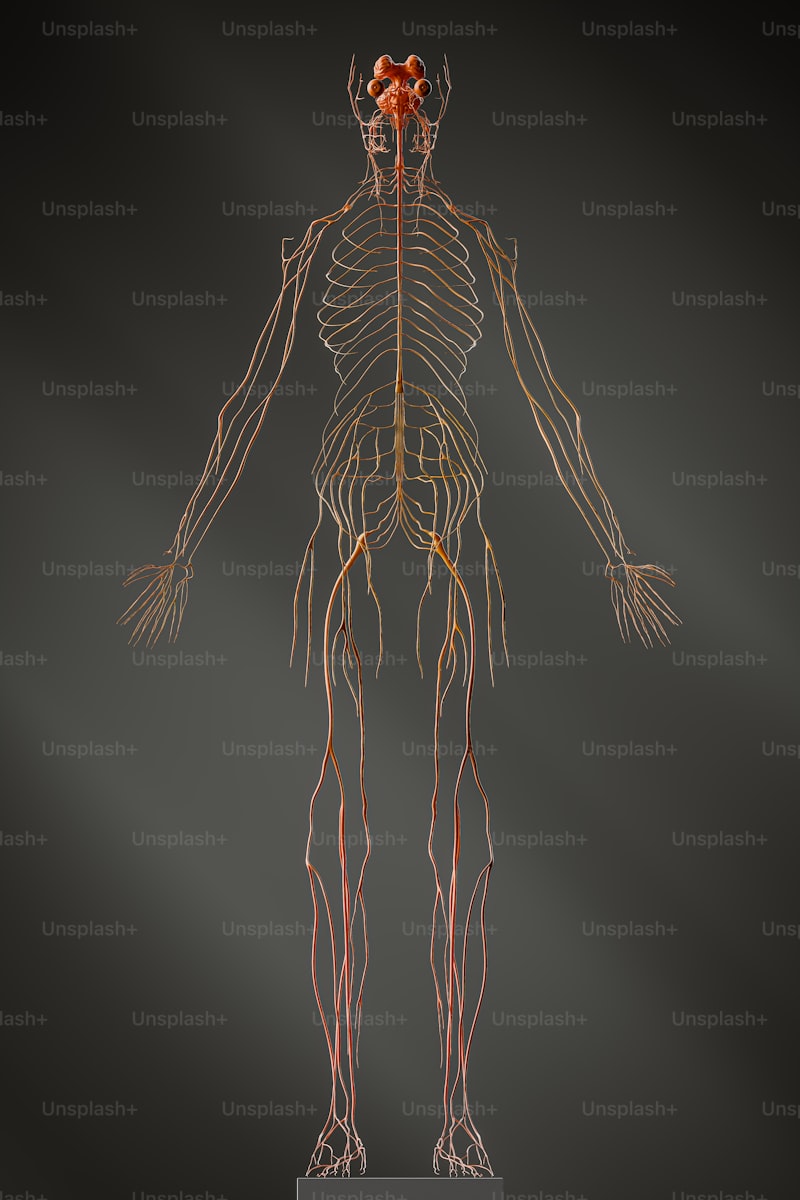

Sinir sistemi, beyin, omurilik ve sinirlerden oluşur. Beyin, vücudumuzu kontrol eden merkezi işlemci gibidir. Omurilik, beynin emirlerini vücudun çeşitli bölümlerine ileten bir yol görevi görür. Sinirler ise bu mesajları taşıyan yollar. Yani, her şey birbiriyle bağlantılı. Sinir sistemimizin sağlığı, düşünme, hareket etme, hissetme ve hatta stresle başa çıkma yeteneğimizi doğrudan etkiler.

Nervium, sinir hücreleri arasında iletişimi sağlayan kritik bir molekül. Sinir hücreleri, elektriksel ve kimyasal sinyaller aracılığıyla bilgi aktarır ve bu süreçte Nervium devreye girer. Düşüncelerinizi hayata geçirebilmek için bu iletişimin kesintisiz olması şart. Sinir sisteme dair küçük bir sorun bile, büyük zorluklara sebep olabilir. Sinir sağlığını desteklemek, günlük enerji seviyenizi ve ruh halinizi olumlu yönde etkileyebilir.

İşte burada stres devreye giriyor. Stres, sinir sisteminin en büyük düşmanlarından biri. Uzun süreli stres, Nervium seviyelerini olumsuz etkileyebilir. Bu da bıkkınlık, kaygı ve fiziksel rahatsızlıkların kapısını aralar. Kısacası, sağlıklı bir sinir sistemi, sağlıklı bir yaşam için temel bir gerekliliktir. Düzenli egzersiz ve dengeli beslenme, Nervium’uniz sağlığını korumak adına etkili yöntemler arasında. Haydi, sağlığınızı göz ardı etmeyin!